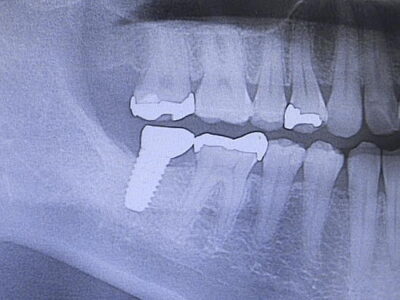

インプラント治療

むし歯や歯周病などの病気や、事故で歯を失った患者様、先天的に歯が足りない方へお勧めしたいのが、インプラント(デンタルインプラント)治療。 インプラントとは、体内に埋め込む医療機器などの人工物や技術。例えば歯を1本失ってしまった場合、欠損部の両側の歯を削り、それを支えにして人工歯を被せる「ブリッジ」という治療が一般的です。ブリッジは支えとなる両側の健康な歯を傷つけてしまいます。そこで歯科治療の選択肢の一つとして、周囲の歯に影響の少ないインプラント治療をおすすめする場合があります。インプラントは、チタン製の人工歯根(フィクスチャー)を顎の骨に埋め込み、その上に土台(アバットメント)と人工の歯(上部構造)を合わせたものです。